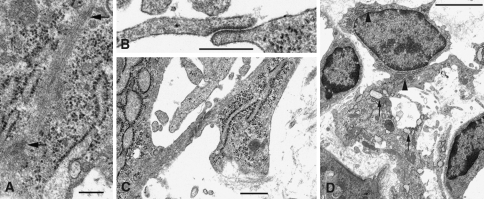

Fig. 3.

Thick ascending limb in the cortex of a sham operated kidney (a) and of a ureter ligated-kidney on day 2 (b); 80 nm epon sections. In b the outer diameters of the tubule as well as the width of the lumen is decreased. c Higher magnification of the area framed in b, revealing junctional complexes (arrowheads) and microvilli. Bars in a, b (same magnification): 5 μm, in d 1 μm

Fig. 5.

Characteristic fibroblasts in a sham-operated kidney (a) and in a ureter-obstructed kidney on day 2 (b). In a the RER (arrow) is flat and concentrated in a cell process whereas the cytoplasmic rim around the angular nucleus is narrow and virtually organelle-free. The fibroblast displays the characteristic narrow association with a tubule and a blood capillary. Collagen fibrils are hardly detectable. The fibroblasts in b reveal inflated cisterns of RER (arrows) distributed all over the cytoplasm, including the direct surroundings of the oval nucleus. In B most collagen fibrils are cross-sectioned and appear as dots (arrowheads). They are abundant along the basement membranes of tubules (lower right and upper left corners). Bars in a and b (same magnification): 2 μm

Fig. 6.

Ultrastructural details of fibroblasts in ureter-ligated kidney (a–c: day 2). a A bundle of actin filaments displays dense bodies (arrows). b Adherent contact between two fibroblasts. c Intercellular contact between two fibroblasts that display different types of RER, inflated on the left, flat as in controls on the right. d Fibroblast in a ureter-ligated kidney (day 4). The profile of the cell reveals large irregularly formed cytoplasmic processes. Different types of RER are visible even within the same cell; in the pericaryon the cisterns are flat (arrowheads), in the large process they are inflated (arrows), masses of collagen fibrils are seen in the immediate vicinity of the process. Bars 0.5 μm and in d 5 μm